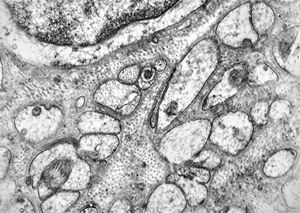

F,32y. | muscular dystrophy - steatosis

F,32y. | muscular dystrophy - regeneratiing muscle cell